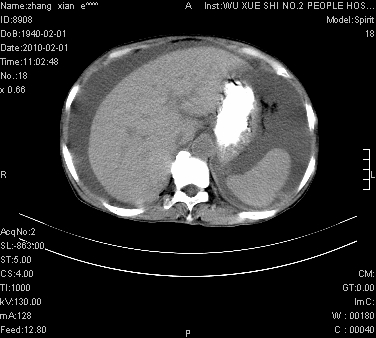

标题: CT24434:70岁 女 腹胀,腹水原因待查 [打印本页]

标题: CT24434:70岁 女 腹胀,腹水原因待查

大量腹水,脾脏囊性占位,子宫颈占位,右侧腹股沟淋巴结肿大,建议+c,先查妇科。

腹盆腔大量积液,子宫增大,子宫颈增大外形不规则,内见低密度影,膀胱后壁显示不清,右腹股沟肿大淋巴结,脾脏囊性占位,子宫颈占位,子宫颈癌?建议增强。

子宫、宫颈占位?转移性腹水?肝性腹水?脾脏囊性占位,囊肿?血管瘤?淋巴瘤?

大量腹水,右肾、脾囊肿可能性大          考虑左侧附件区占位,建议增强